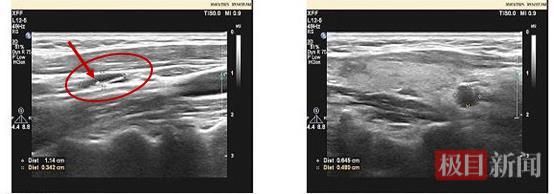

右侧颈部Ⅲ区、V区淋巴结结构异常(Ⅲ区一个伴钙化)

在诊疗过程中,最大的挑战集中在孙女士右侧颈Ⅲ、Ⅳ区淋巴结的评估上。超声影像提示该区域淋巴结结构异常,其中Ⅲ区一个伴有钙化的淋巴结尤为可疑。这个淋巴结的性质判断至关重要,将直接决定最终手术范围的划定。